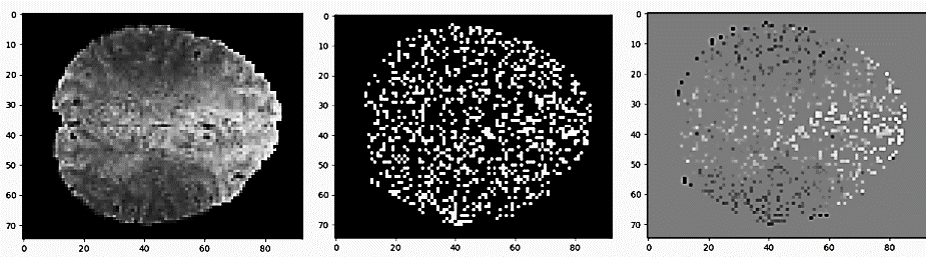

The second loss is an intensity loss, denoted as L1bsuperscriptsubscriptL1b\pazocal{L}_{1}^{b}. This loss is based on an L1 applied to a subset of the voxels associated with local intensity values, which are more likely to represent a relevant BOLD signal. More specifically, given a full scan, (x1,,xn)subscript𝑥1subscript𝑥𝑛(x_{1},\dots,x_{n}), we infer the voxel-normalization Xvsuperscript𝑋𝑣X^{v}. Then, for each voxel-normalized frame xivXvsuperscriptsubscript𝑥𝑖𝑣superscript𝑋𝑣x_{i}^{v}\in X^{v}, we set xivqpk=0subscriptsuperscriptsubscript𝑥𝑖𝑣𝑞𝑝𝑘0{x_{i}^{v}}_{qpk}=0 if |xiv^qpk|<bsubscript^superscriptsubscript𝑥𝑖𝑣𝑞𝑝𝑘𝑏|{\hat{x_{i}^{v}}}_{qpk}|<b and xivqpk=xiv^qpksubscriptsuperscriptsubscript𝑥𝑖𝑣𝑞𝑝𝑘subscript^superscriptsubscript𝑥𝑖𝑣𝑞𝑝𝑘{x_{i}^{v}}_{qpk}={\hat{x_{i}^{v}}}_{qpk} otherwise, where b𝑏b is a threshold value configured as the 80% quantile of the absolute of the voxel-normalized values, inside the anatomy and across the sub-sequence. The motivation behind the elimination of the voxels associated with the 80% of the values that are closer to 0 is that these values are typical across many frames, and are therefore unlikely to represent a distinctive signal. An illustration of the intensity loss is depicted in Fig. 5 in the supplementary appendix.

Figure 3: A representative sample of a slice (left) and its voxels that contribute to the intensity loss (right). The intensity loss emphasizes the voxels that vary the most in a given frame, by leveraging a “focused” L1 loss applied to those specific voxels. To calculate this loss, we infer a binary mask for each of the slices (middle).

The intensity loss L1bsuperscriptsubscriptL1b\pazocal{L}_{1}^{b} is based on an L1 loss applied to a subset of the temporally-intense voxels, which are more likely to represent a relevant BOLD signal. The intensity loss eliminates voxels associated with 80% of the values that are close to 0 were eliminated since they are typical across many frames and are therefore unlikely to represent a distinct signal. A representative slice and its voxels associated with the intensity loss can be seen in Fig. 3.